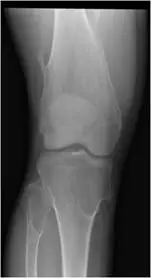

20 歲男性,因右膝受傷接受 X光攝影。附圖為 X光攝影影像,最可能的診斷為何?

遺傳性多發性外生骨疣(hereditary multiple exostoses, HME),又稱遺傳性多發性骨軟骨瘤(hereditary multiple osteochondromas, HMO),是一種體染色體顯性遺傳疾病,特徵為多個骨軟骨瘤在全身長骨的骨骺端(metaphysis)對稱性或不對稱性形成。本題考核膝關節 X 光上多發性骨突病灶的診斷辨識。

膝關節正位及側位 X 光顯示以下特徵:

正位(AP view):

- 股骨遠端及脛骨近端的骨骺端(metaphysis)可見多個骨性突起(bony exostoses/osteochondromas)

- 突起的骨皮質與骨髓腔與宿主骨(host bone)呈連續性延伸,此為診斷骨軟骨瘤的關鍵特徵

- 突起呈無蒂(sessile)型態

- 骨幹/骨骺端有寬大表現(Erlenmeyer flask deformity,燒瓶狀變形),為 HME 的典型骨骼發育異常

- 無侵襲性骨質破壞、無骨膜反應、無軟組織腫塊

多發性、對稱性分佈、骨骺端發生、骨皮質連續延伸的骨性突起,高度